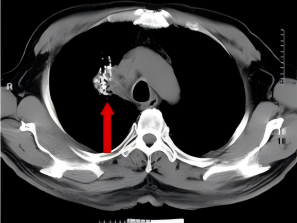

68岁患者,因长期咳嗽、气喘、气急等症状前来我院呼吸与危重症医学科就诊,在进行CT检查后,发现患者右肺存在肿瘤,进一步完善相关检查后,诊断为右肺鳞癌IIIB期,因考虑到患者肿瘤较大,需切除大部分肺组织,对肺功能影响非常大,在充分尊重患者意愿下,科室为患者制定了多种治疗方案,最终患者选择了CT引导下经皮肺穿刺碘125粒子植入治疗。综合治疗5月后,患者病灶明显缩小,2年后复查,患者病灶稳定。

碘125粒子植入术后

综合治疗5月后

综合治疗2年后